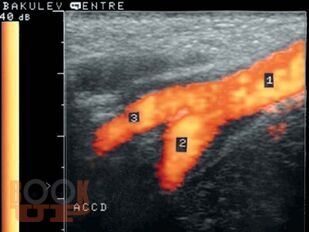

В атласе представлены разделы, посвященные ультразвуковой диагностике заболеваний сонных артерий, позвоночных артерий, плечеголовного ствола, подключичных артерий, артерий верхних конечностей, аортоподвздошного сегмента, бедренных и подколенных артерий, артерий голени, вен

нижних конечностей, а также оценке эффективности хирургической реконструкции сосудов нижних конечностей и ультразвуковой диагностике сочетанных аномалий развития ветвей дуги аорты при коарктации аорты. В указанных разделах представлен огромный клинический материал (800 эхограмм, спектрограмм и схем), методически организованный на основе многолетнего опыта работы автора в

Научном центре сердечнососудистой хирургии им. А.Н. Бакулева РАМН.